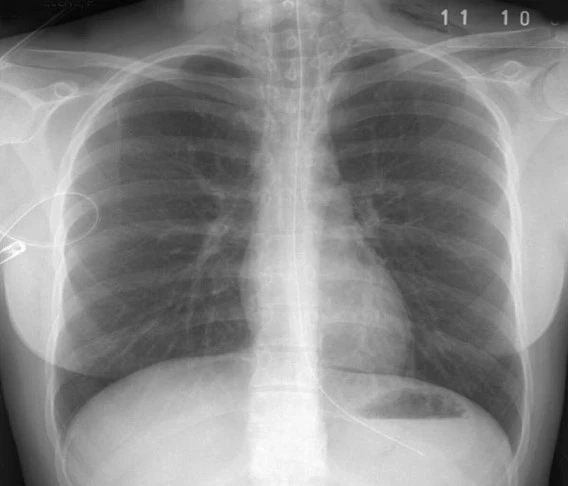

4. Цээжний X-ray-д илрэх өвчинийг Cases дээр тайлбарлах

MNT 30,000.00 or Chest X-Ray